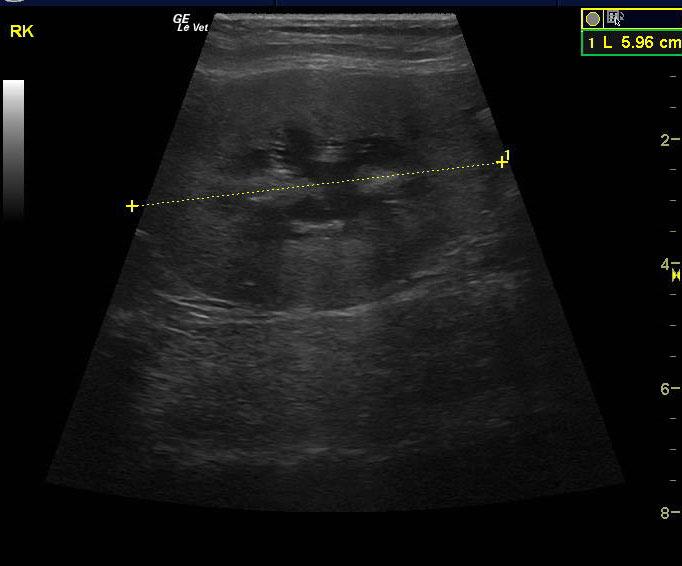

A 15 year old spayed female DMH cat was presented for progressive disease over a 6-8 month period, characterized by poor coat quality, decreased mobility, reduced activity, and pruritic skin lesions that have not responded to antibiotics and use of an E-collar. Abnormalities on physical examination were alopecia, hyperpigmentation, and thinning of the skin of the ventrum, and a non-healing, plaque-like, superficial skin lesion on the cranial aspect of the left stifle and accessory pad of the left carpus. Skin biopsies were scheduled. On urinalysis an inappropriate SG and proteinuria was present with a urine protein: creatinine ratio of 0.3. Abnormalities on serum biochemistry included hypercalcemia and hyperproteinemia. Radiographs showed arthritis of elbow, LS junction, and hips, as well as a mass in the region of the left kidney.